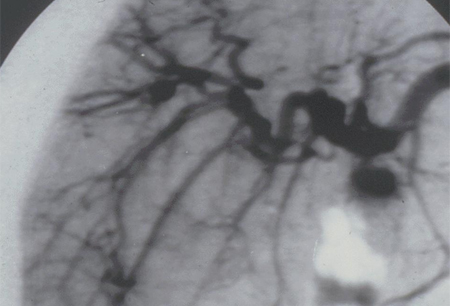

A angiografia convencional é a modalidade de exame de imagem de escolha e deve ser realizada caso haja suspeita clínica de PAN. A sensibilidade relatada é de 89%. A especificidade é de 90% quando realizada em pacientes com suspeita de vasculite.[40] Achados clássicos incluem pequenos aneurismas múltiplos, ectasia vascular e lesões oclusivas focais em vasos de tamanho médio, mais tipicamente nas artérias renais e mesentéricas.

[Figure caption and citation for the preceding image starts]: Angiografia mesentérica mostrando pequenos aneurismas e microaneurismasDo acervo do Dr Loic Guillevin [Citation ends].